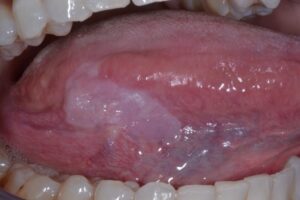

عفونت فک و صورت چیست و چرا باید آن را جدی بگیریم؟

این عفونت‌ها وقتی پیش می‌آیند که چرک در بافت‌های نرم، مثل پوست و عضله‌های صورت، یا حتی استخون فک جمع می‌شود، اما چرا این موضوع انقدر مهم است؟

پوسیدگی که به ریشه دندان رسیده، لثه‌های ملتهب یا دندان عقل گیر کرده داخل فک، می‌توانند باکتری را به جاهای عمیق‌تر ببرند.

بافت‌های این بخش به یکدیگر وصل هستن و عفونت می‌توانددر همه جاها و قسمت‌های بدن پخش شود. از ریشه دندان شروع و به گونه برسد، زیر زبان، یا حتی عمق گردن. اگر به راه تنفسی فشار وارد کند یا وارد خون شود، اوضاع بسیار بدتر از پیش از آن می‌شود.

علائم قابل توجه و مهم عارضه عفونی فک و صورت کدامند؟

اگر زود متوجه علائم حساس ضایعات عفونی فک و صورت مثل موارد زیر شویم، درمان خیلی راحت‌تر پیش می‌رود، این موارد چندتا از علامت‌های مهم به شمار می‌آید: